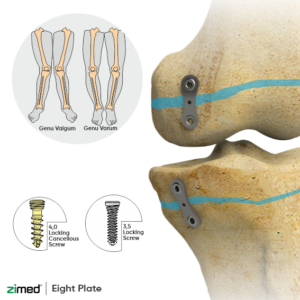

Eight Plates